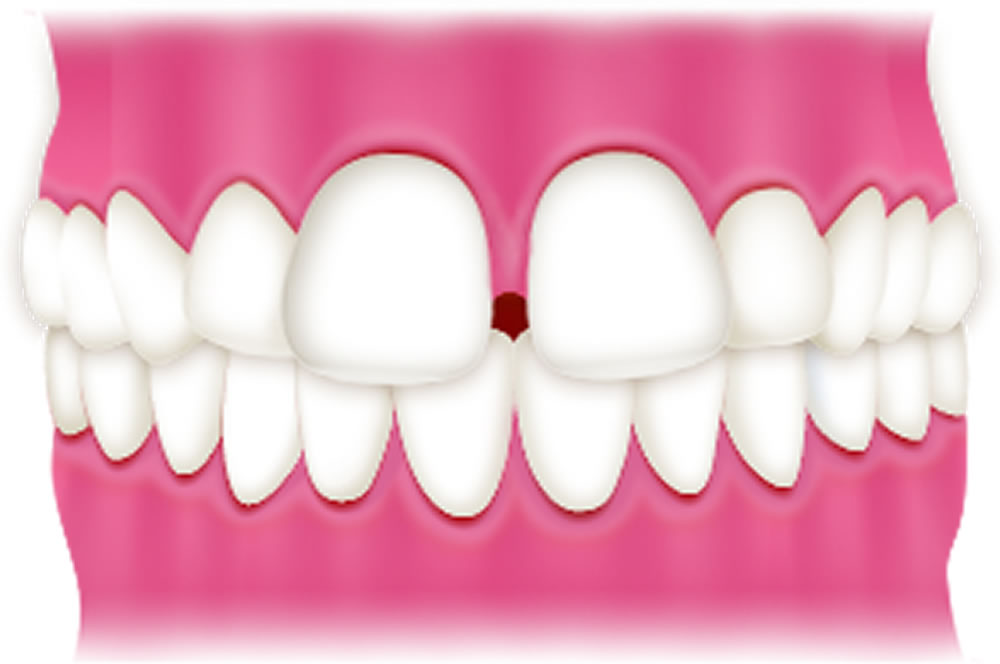

すきっ歯

歯と歯の間にすき間がある状態です。汚れが溜まりやすく、虫歯や歯周病のリスクが高まります。また、空気が漏れやすく、発音に影響が出ることがあります。